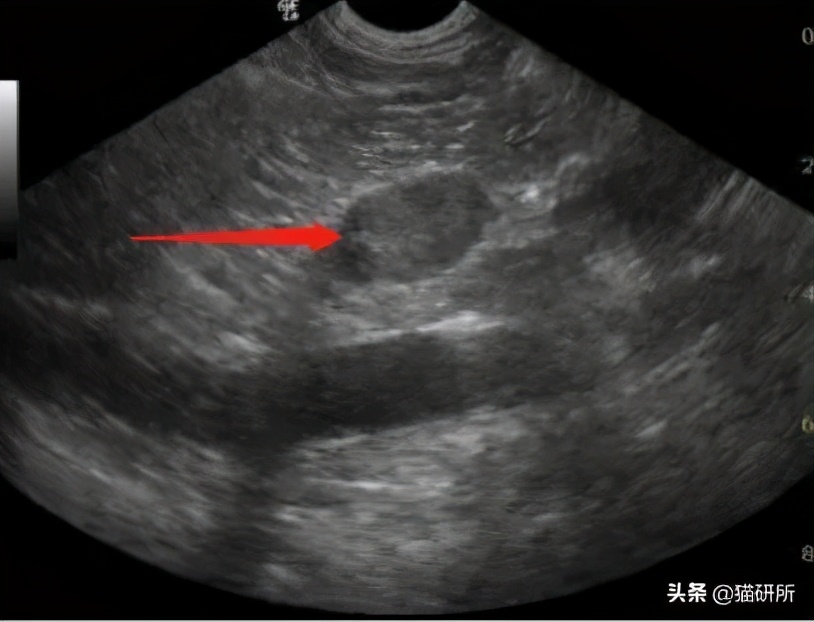

- 影像学检查

X线、B超可以评估猫咪的子宫、卵巢、*丸睾**、前列腺等内部器官的情况。